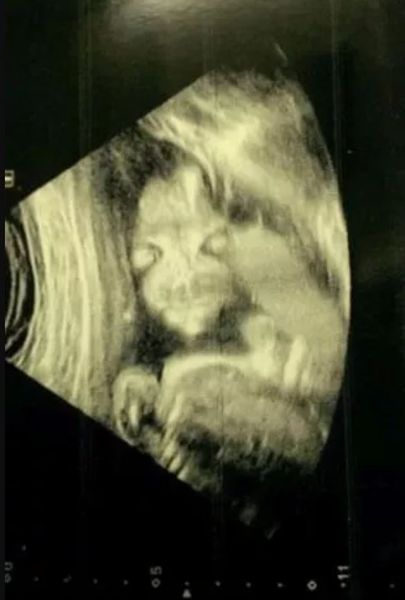

Джейд Бойланд с нетерпением ждала, чтобы посмотреть на первое изображение своего будущего ребенка, но во время УЗИ была в оцепенении, увидев жуткую фигуру, напоминающую пришельца. По словам матери из города Чард (графство Сомерсет, Великобритания), малыш напомнил ей зловещего персонажа из мультфильма "Салатные пальчики". Об этом случае пишет издание The Mirror.

Будущая мама с нетерпением ждала результатов сканирования, ожидая классический снимок ребенка в профиль, чтобы потом повесить его на холодильник или отправить друзьям. Но то, что она получила, вызвало настоящий шок. Нерожденный плод на снимке лежал лицом к ней и выглядел довольно жутко, чем-то напоминая героя мультфильма, нарисованного Дэвидом Фертом.

Фото: Jade Boyland | Facebook

Джейд вспомнила, как врач начала громко смеяться, когда проводила сканирование, а потом успокоила ее, что все в порядке.

"Она была похожа на "Салатные пальчики" с большими глазами и длинными пальцами. Женщина, которая делала сканирование, начала смеяться. Это меня сначала испугало, потому что я не знала, все ли хорошо. Спросила: "Что такое?". Тогда врач объяснила, что плод повернут к нам лицом", — рассказывает Бойланд.

По ее словам, друзья и родственники хохотали, когда увидели снимок, сделанный еще в 2014 году, когда она была на 20 неделе беременности. К счастью, ребенок появился на свет путем кесарева сечения абсолютно здоровым. Впрочем, тогда Джейд провела несколько месяцев, волнуясь о том, как девочка будет выглядеть после рождения.